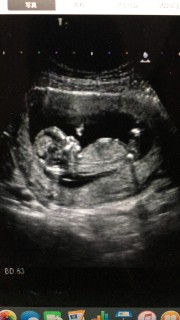

つわりはひどいのに子供はすくすく成長してくれてるようです。6.06㎝ぐらいの大きさに。 寝てたのか動き見れなかったので次回に期待してます♡

2人目です。CRL4.77cmで少し小さめだそう。でも元気に動いてたので、問題はないとの事。上は男の子。次はどっちかなー